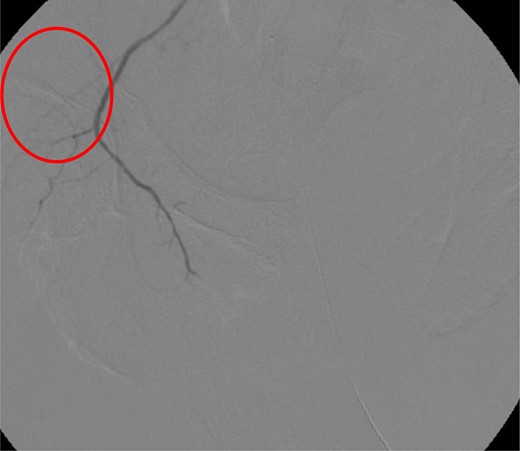

CT abdomen/pelvis with contrast was performed and a blush of contrast was noted posterior to the right pubic bone. Prior to taking patient for exploratory surgery, he was transferred to the interventional radiology suite where a pelvic angiogram was performed revealing an abnormal blush localized to the distal branches of the right iliolumbar artery (Fig. 2). Delayed phase of the angiogram demonstrated early venous filling consistent with a traumatic arteriovenous fistula which was embolized with 300–500 µ of embospheres and three 3 × 2 microcoils (Figs 3 and 4).

CT angiogram demonstrating microcoil embolization of AV fistula.